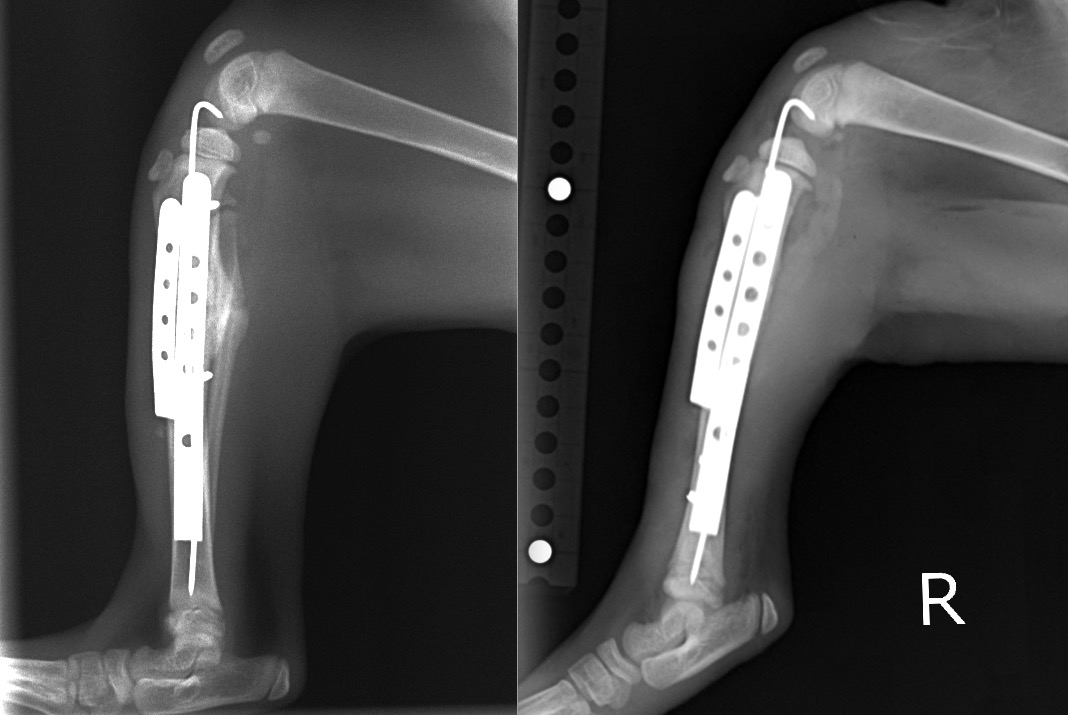

術直後、2週間後、4週間後のX線写真です。

術後4週間/術直後